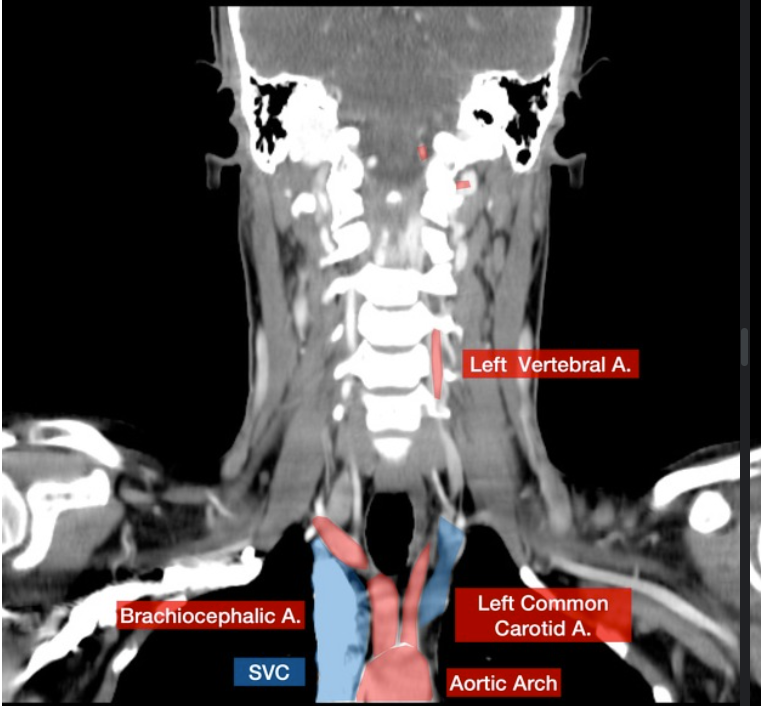

Please label this coronal CT scan